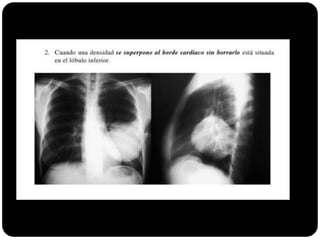

Sinal da silhueta

Lobo médio: borra o contorno direito do coração.

Língula: borra o contorno esquerdo do coração.

Segmentos basais: borram o contorno do diafragma*** (olhar

imagens anteriores para ver quais).

1. Qual lobo está afetado? Por quê?

É atelectasia?

Lobo

médio(segmento

medial e lateral;

Borra contorno

cardíaco direito

E não é atelectasia!

A fissura horizontal

não está deslocada.